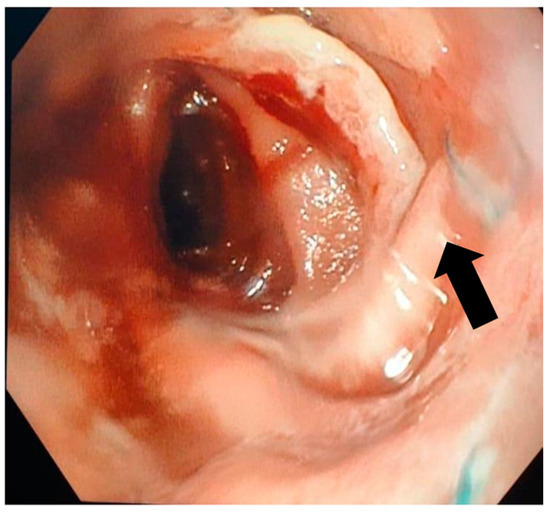

In terms of the surgical outcomes, three surgical techniques were used on most of the patients (Table 2): Ivor Lewis (17 patients) with eso-gastric anastomosis, McKeown (4 patients) with eso-cervical gastric anastomosis, and total gastrectomy with esophago-jejunostomy (34 patients). There was one patient who had also a partial hepatectomy due to tumoral invasion in the liver, and one who had a partial gastrectomy. In our study, only complete cover stents were used, with four stent sizes. The average period for stent usage was 32.4 days with an average period of 7.4 days post-surgery at which a fistula was diagnosed. We have to mention that there were no patients that had immediate post-surgical leakage present at the methylene blue leak testing. The average hospital stay by anastomosis type was 19.1 days for eso-gastric anastomosis, 4.5 days for the eso-gastric cervical anastomosis, and 8.9 for the eso-jejunal anastomosis. Patient survival was 95%, with a total death count of three. The fistula closure rate was 98% (54 patients), with 2 patients (out of 54) not surviving due to later complications. However, post-stenting complications were more often present, with a rate of 20% (11 patients). Most often the complications were stent migration (Figure 4), stent-induced hemorrhage (Figure 5) and stent perforation. There were 12 cases of post-stenting mediastinitis, out of which 2 resulted in patient death. Another death was due to an aortic-esophagus fistula.

Stenting as an efficient means of AF resolution had favorable results in our patient group, showing a primary efficiency of 90% after the first stent placement and a secondary efficiency of 98%, after the second stent, having an overall survival rate of 95%. These findings exceed the results cited in the medical literature, where primary and secondary efficiency was defined as 50% and 70%, respectively [31,38], proving the superiority and efficiency of endoscopic stenting as a treatment for AF. In addition, the post-stenting complication rate in our study was 20% (11 patients), considerably decreased compared to an average complication rate of 46% in the study of Fabbi et al. [10], which may be due to a different selection of the patients that should undergo this procedure. Among the most common complications of the stenting procedure, we found migration in three patients, stent-induced hemorrhage in six patients and stent perforation in two patients. Analyzing the risk of the migration associated with a small-sized stent, we concluded the absence of statistical correlation between the stent dimension and the higher risk of post-stenting complication (p = 0.12).

Figure 5. Endoscopic appearance of an esophageal stent-induced hemorrhage at the esophageal end of the stent inserted for the closure of an eso-jejunal anastomotic fistula.